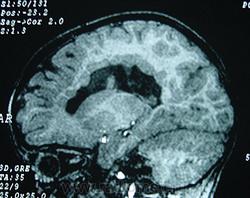

Гетеротопии. Перивентрикулярная гетеротопия. Субэпендимальная нодулярная (узелковая) гетеротопия.

Наиболее частым вариантом миграционных нарушений является гетеротопия - скопление нейронов, остановившихся в различных аномальных местах на пути следования к коре головного мозга. Такая остановка происходит не позже 5-го месяца внутриутробного развития. Изолированный участок узловатой массы называется «гетеротопион». В настоящее время описаны следующие варианты гетеротопии:

- субэпендимальная нодулярная (узелковая) гетеротопия;

Перивентрикулярная субэпендимальная гетеротопия